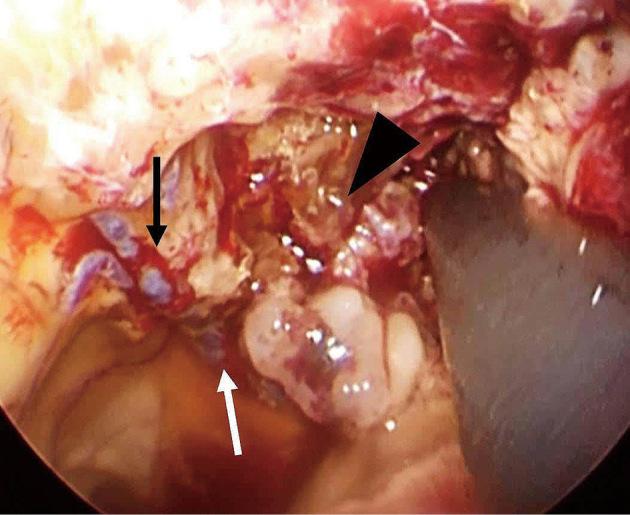

Subependymoma (SE) is a rare, usually asymptomatic, brain tumor predominantly affecting older adults and occurring in the fourth and lateral ventricles. We report a rare case of SE with intratumoral hemorrhage that could be removed by neuroendoscopy. The 81-year-old patient had been followed as an outpatient for 10 years due to an intraventricular tumor. It did not grow over the patient's lengthy follow-up. The patient was transferred to our hospital after he fainted near his home; at the time of admission, he had mild consciousness disturbance, and his Glasgow Coma Scale score was 10 points (E3V3M4). Computed tomography showed intratumoral hemorrhage and slight ventricular enlargement. Magnetic resonance (MR) imaging showed a 4 cm-sized tumor in the anterior horn of the right lateral ventricle. The lesion appeared as a mixed-intensity solid tumor and showed irregular enhancement with gadolinium. The patient underwent neuroendoscopic tumor resection on the 30 day of the patient's hospital stay. A histopathological examination revealed small tumor cells with round nuclei scattered in the glial fibrillary background. Immunostaining was positive for glial fibrillary acidic protein; these findings are consistent with an SE diagnosis. The patient in this study had hypertension and used anticoagulants, risk factors for intratumoral hemorrhage. For intraventricular tumors with bleeding-particularly in older or more physically frail patients-minimally invasive neuroendoscopic surgery should be considered an option for tumor resection.

室管膜下瘤(SE)是一种罕见的、通常无症状的脑肿瘤,主要影响老年人,多发生于第四脑室和侧脑室。我们报告一例罕见的伴有瘤内出血的室管膜下瘤,该肿瘤可通过神经内镜切除。这位81岁的患者因脑室内肿瘤已作为门诊患者随访了10年。在患者漫长的随访期间肿瘤未生长。患者在家附近晕倒后被转至我院;入院时,他有轻度意识障碍,格拉斯哥昏迷量表评分为10分(E3V3M4)。计算机断层扫描显示瘤内出血和轻度脑室扩大。磁共振成像显示右侧脑室前角有一个4厘米大小的肿瘤。该病变表现为混合密度实性肿瘤,钆增强扫描显示不规则强化。患者在住院第30天行神经内镜肿瘤切除术。组织病理学检查显示圆形核的小肿瘤细胞散在于胶质纤维背景中。免疫染色胶质纤维酸性蛋白呈阳性;这些发现符合室管膜下瘤的诊断。本研究中的患者患有高血压并使用抗凝剂,这些都是瘤内出血的危险因素。对于伴有出血的脑室内肿瘤,尤其是老年或身体较为虚弱的患者,微创神经内镜手术应被视为肿瘤切除的一种选择。